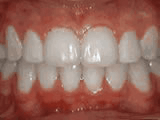

Crowding of the teeth

Patient started treatment at age 11 and wore braces for 26 months. He loves his new smile.